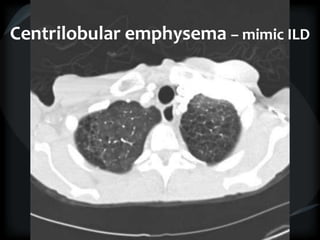

Bronchiectasis – ILD mimic

Centrilobular emphysema – mimic ILD